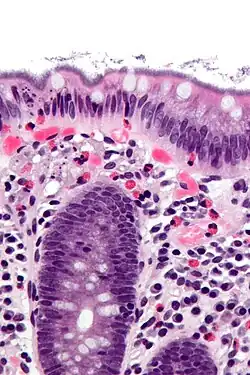

| Histopathology of intestinal spirochetosis, showing basophilic, fringe-like, end-on-end attachment of filamentous densely packed spirochetes on the surface epithelium of the intestinal mucosa.[1] H&E stain. | |

It is diagnosed by examination of tissue, i.e., biopsy. A hallmark finding is the presence of a “false brush border” on the luminal surface of the epithelium, formed by dense linear colonization of spirochetes.[4]

- ^ Image by Mikael Häggström, MD. Reference for description: Elliot Weisenberg, M.D. "Intestinal spirochetosis". Pathology Outlines. Last author update: 1 May 2017. Last staff update: 3 May 2022